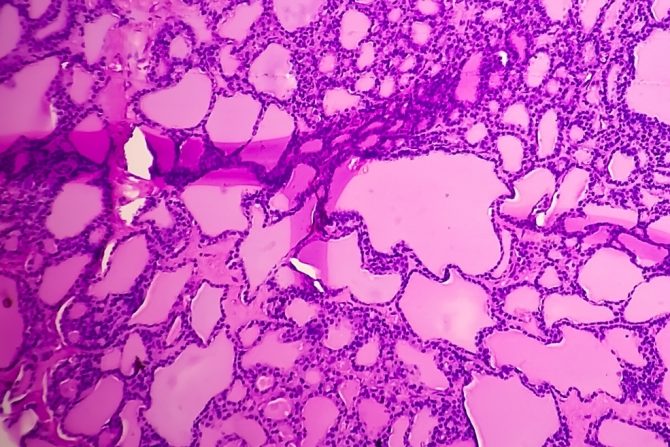

Sinovijalne sarkome nije lako dijagnostikovati, jer se pokazalo da se ovi karcinomi razvijaju sporo. U proseku, ljudi sa sinovijalnim sarkomom imaće simptome 2 godine pre nego što dobiju dijagnozu. Kada lekari posumnjaju na sinovijalni sarkom, prvoće preporučiti magnetnu rezonancu, MR skeniranje. Ova tehnika daje pouzdano tačne slike sarkoma mekog tkiva. Ako MR skeniranje otkrije tumor, lekari mogu da nastave sa testiranjem. Kako bi razlikovali sinovijalni sarkom od drugih sarkoma mekog tkiva, radi se biopsija, kao i hirurška procedura za uklanjanje tkiva iz tumora. Uzorak tumora zatim se testira u laboratoriji.